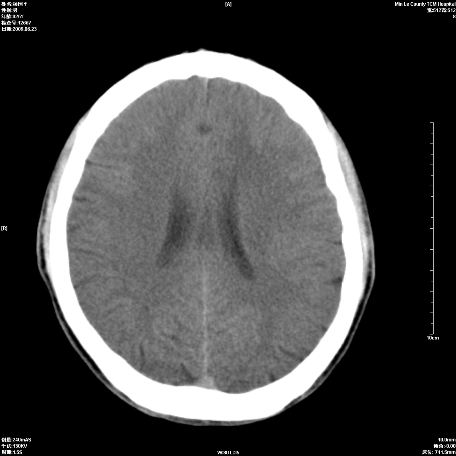

以下是引用zxl51642在2009-6-23 14:15:00的发言:[br]1、颅内未见血肿,颅骨未见骨折;[br]2、双侧苍白球对称性钙化,透明隔间腔及verga氏腔形成。